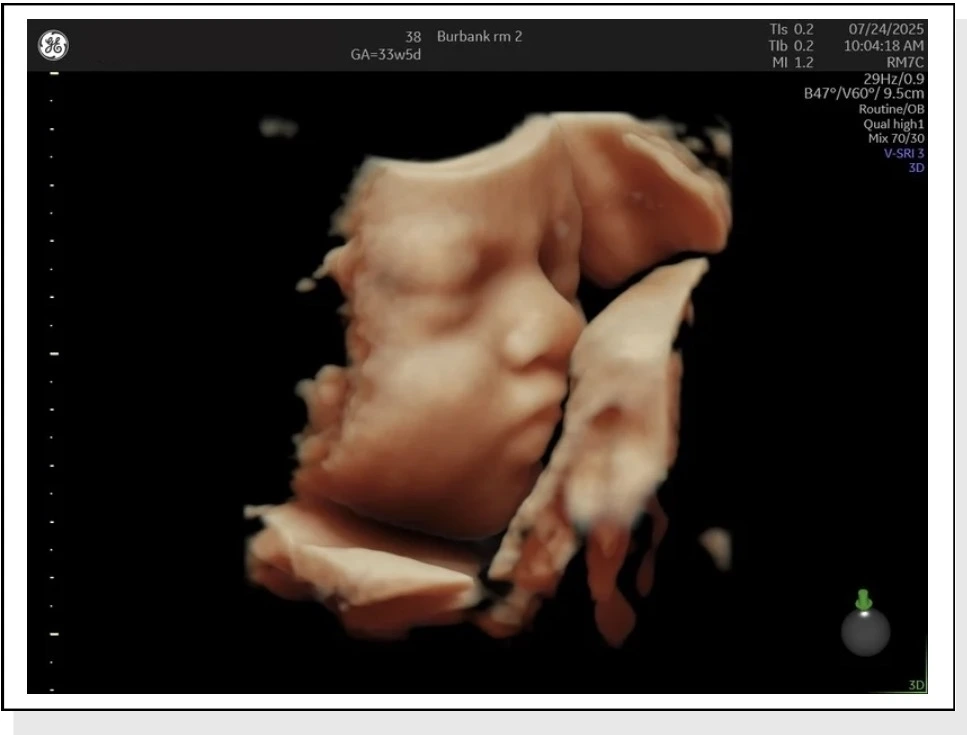

Women with uncomplicated pregnancies seeking first-class ultrasound services – Providing high-quality imaging, including 3D/4D ultrasounds, to ensure comprehensive and accurate prenatal evaluations.